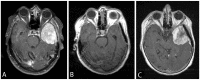

Methods: We characterized 64 temporally- and regionally-distinct specimens from 26 WHO grade III meningioma patients. On initial diagnoses, the meningiomas spanned all WHO grades (3 grade I, 13 grade II and 10 grade III). The tumor samples were screened for TERTp and ATRX/DAXX mutations, and TERT rearrangements. Additionally, TERTp was sequenced in a separate cohort of 19 patients with radiation-associated meningiomas. We examined the impact of mutational status on patients' progression and overall survival.

Results: Somatic TERTp mutations were detected in six patients (6/26 = 23%). Regional intratumoral heterogeneity in TERTp mutation status was noted. In 4 patients, TERTp mutations were detected in recurrent specimens but not in the available specimens of the first surgery. Additionally, a TERT gene fusion (LPCAT1-TERT) was found in one sample. In contrary, none of the investigated samples harbored an ATRX or DAXX mutation. In the cohort of radiation-induced meningiomas, TERTp mutation was detected in two patients (10.5%). Importantly, we found that patients with emergence of TERTp mutations had a substantially shorter OS than their TERTp wild-type counterparts (2.7 years, 95% CI 0.9 - 4.5 years versus 10.8 years, 95% CI 7.8 -12.8 years, p=0.003).